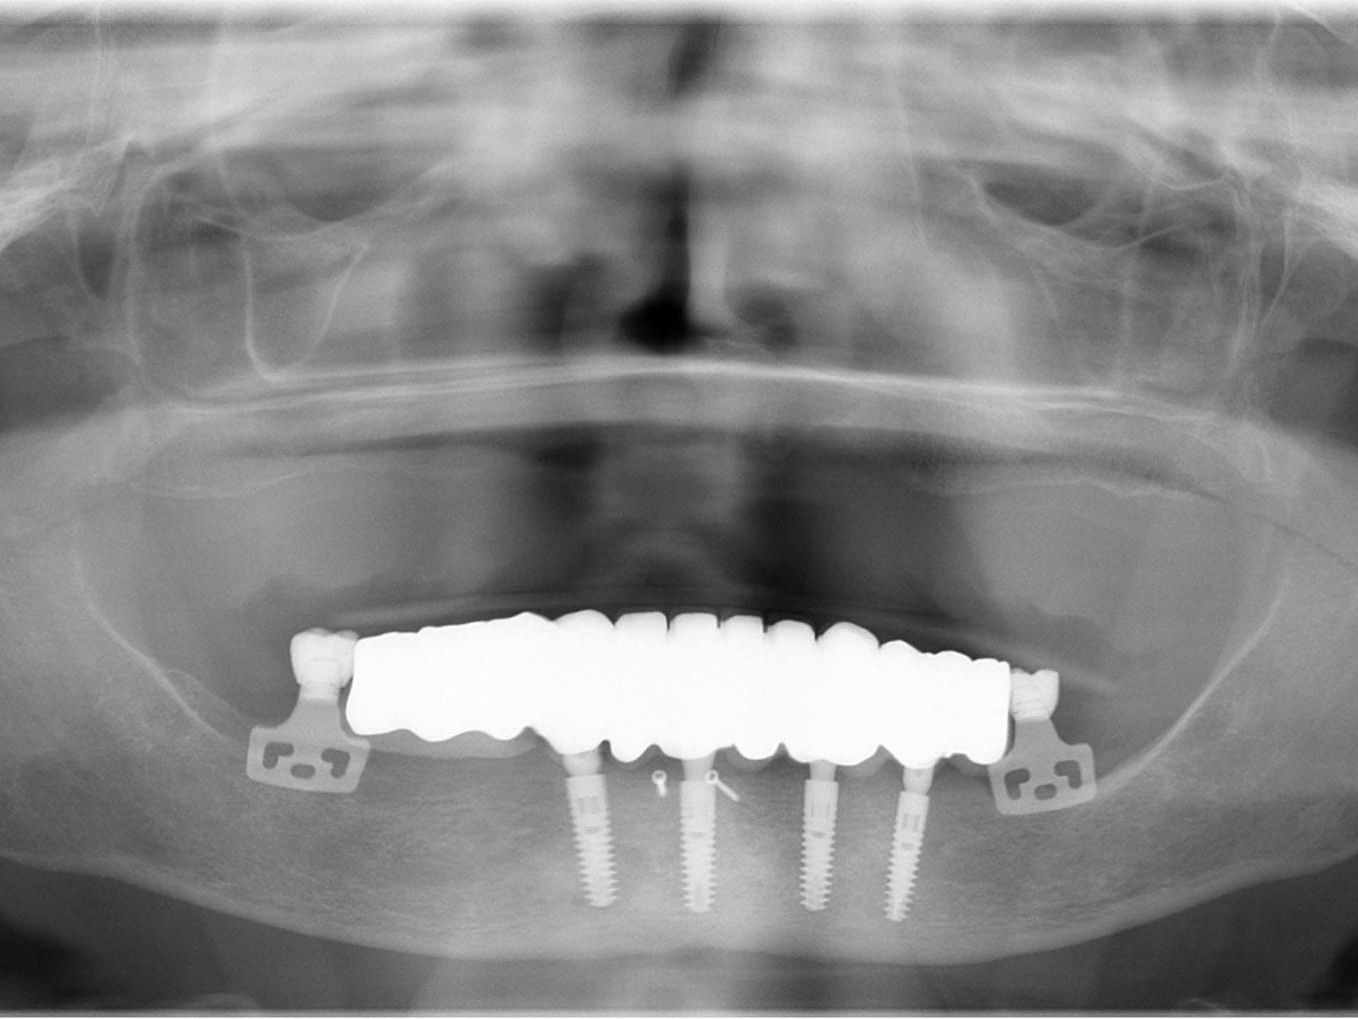

Für die Allgemeinanästhesie erfolgte zunächst die zusätzliche Gabe eines typischen Infiltrationsanästhetikums. Intravenös wurde unmittelbar präoperativ das Antibiotikum Clindamycin 600 mg gegeben. Abbildung 7 zeigt die klinische Ausgangssituation linksseitig. Nach der vorsichtigen Durchtrennung der Brückenkonstruktion (Abb. 8) jeweils vor der Krone auf den Blattimplantaten und Entfernung der nicht erhaltungswürdigen Zähne 44 bis 33 samt ihrer Überkronung (Abb. 9) wurde der Mukoperiostlappen vestibulär wie lingual passend zur erstellten Schablone präpariert und die Bohrschablone in ihrer finalen Lage eingebracht (Abb. 10). Zunächst erfolgte die Insertion der angulierten Implantate Ankylos ® C/X-Implantate (Durchmesser 3,5 mm) der Länge 14 mm in regio 034 (Abb. 11 und 12) und 044. Danach wurden in den Positionen 032 und 042 jeweils ein weiteres Ankylos ® C/X –A-Implantat mit gleicher Länge und Durchmesser inseriert (Abb. 13). Sämtliche entfernten Knochenpartikel und auch Bohrspäne wurden akribisch asserviert. In den Positionen 032 und 042 wurden Ankylos ® Balance Basisaufbauten C/ (GH 3,0 / Ø 5,5 mm, Kopfhöhe 2,4 mm) mit 15 N/cm eingeschraubt. Anschließend hat der Zahntechniker mittels der Ankylos ® Modellierhilfskappenfür den Balance Basisaufbau Retentionskappen hergestellt, die mit 25 N/cm eingebracht wurden (Abb. 14). Am Implantat regio 042 wurde der Knochen in Schalentechnik nach vestibulär aufgebaut (Abb. 15)⁹,¹⁰. Im nächsten Schritt haben wir die angulierten Ankylos ® Balance Basisaufbauten C (nicht indexierte Abutments) in Regio 034 und 044 (GH 3,0, A30 / Ø 4,2 mm, Kopfhöhe 1,3 mm) ausgerichtet und ihren spezifischen Vorgaben entsprechend eingebracht (Abb. 16). Nachdem sich alle erforderlichen prothetischen Implantatbauteile in situ befanden (Abb. 17), erfolgte die Überprüfung und geringfügige Anpassung des im Vorfeld digital erstellten Sofortprovisoriums. Im Anschluss wurden die leeren Alveolen und Knochendefekte mit dem gewonnenen autologen partikulären Material aufgefüllt. Dann erfolgte der typische Naht-Wund-Verschluss mit Einzelknopfnähten eines resorbierbaren Nahtmaterials (Abb. 18). Nachdem die Patientin aus der Vollnarkose erwacht war und ihre motorischen Fähigkeiten wiedererlangt hatte, wurde das Sofortprovisorium eingesetzt und in Okklusion gebracht. In dieser Position wurden die Retentionskappen über ein selbsthärtendes fluoreszierendes kaltpolymerisierendes Paste-Kartuschensystem fixiert. Anschließend erfolgte die extraorale Versäuberung des Interimszahnersatzes. Nach Refixierung des Sofortprovisoriums in der Mundhöhle (Abb. 19 und 20) und dem Verschluss der Schraubenkanäle mit Kunststoff erfolgte die radiologische Kontrolluntersuchung (Abb. 21).

Nach erneuter Überprüfung der implantatprothetischen Sofortversorgung auf sämtliche okklusalen und gelenkspezifischen Parameter erfolgte die Abformung im Ober- und Unterkiefer (Abb. 22). Da die Ankylos Balance-Basis Aufbauten intraoperativ bereits zum Zeitpunkt der Interimsversorgung definitiv eingesetzt wurden, erfolgte die Abformung auf Abutmentniveau mit einem Folienlöffel für präzise Implantatabformung. Um die visuelle Kontrolle über den Abformprozesses zu haben, kam ein transparentes Abformmaterial zur Anwendung. Zur präzisen Übertragung der Mundsituation auf das Modell ist entweder eine zweite Abformung mit einem entsprechenden laborgefertigten Kontrollschlüsssel oder eine direkte intraorale Verblockung der Ankylos Abformpfosten erforderlich¹¹. Bei der letztgenannten Variante werden die direkte Verblockung der Abformpfosten und die präzise Implantatabformung miteinander kombiniert (Abb. 23). Hierfür wird Zahnseide spannungsfrei mehrfach über Kreuz um die Abformpfosten geschlungen. Das hieraus entstehende Gerüst dient als Trägerplattform für das Autopolymerisat, das wir in Pinseltechnik appliziert haben. Um ein zügigeres Arbeiten am Patienten zu gewährleisten, kamen vorgefertigte Stangen (Ø 3 mm) aus rotem Modellierkunststoff zum Einsatz. Dieser Modellierkunststoff zeigt auch bei sehr dünnen Schichtstärken eine minimale Schrumpfung bei hoher Festigkeit sowie Stabilität. Das zeitversetzte Applizieren des Autopolymerisates gewährleistet die Spannungsfreiheit der Verblockung. Das Meistermodell wurde aus Klasse–IV-Superhartgips mit typischer Gingivamaske hergestellt. Bei weitspannigen Suprastrukturen lässt sich die höchste Genauigkeit mit einer verblockten Präzisionsabformung erreichen. Die durch das nach distal ausgedehnte prothetische Polygon bedingte Weitspannigkeit ist das Prinzip des SmartFix-Konzeptes. Nach der Modellherstellung erfolgte die anatomisch korrekte Übertragung der Schädel-Achs-Relation des Oberkiefers in den Artikulator mittels Gesichtsbogen. Zur Montage des Unterkiefers konnte in diesem Fall auf eine klassische Bissnahme verzichtet werden, da das computerdesignte und okklusal verschraubte Langzeitprovisorium während der Einheilphase vom Behandler feinjustiert wurde und somit die Bisshöhe und -lage zur Übertragung perfekt geeignet war. Hierfür wurde das Provisorium entnommen, so dass der Zahntechniker die Artikulation und die damit verbundene Individualisierung der Artikulatorenwerte in der Praxis vornehmen konnte. Im Labor erfolgte die komplette Digitalisierung des Falles. Der gesamte Workflow dieses Patientenfalles beruht auf dem Prinzip des Backward Plannings. Dem Team, bestehend aus einem implantatchirurgischen und einem implantatprothetischen Behandler sowie einem Zahntechniker, ist daran gelegen, sowohl chirurgisch als auch prothetisch vorhersagbare Ergebnisse zu generieren. Bei einer okklusal verschraubten Brücke ist es für den Zahntechniker vor Beginn der Arbeit wichtig, den späteren Austrittspunkt der Schraubenkanäle zu kennen und eine diagnostische Aufstellung in Form und Funktion anzufertigen. Nur so wird gewährleistet, dass das CAD/CAM gefertigte Gerüst die Verblendungen optimal unterstützt und die Schraubenkanäle ideale Durchtrittspunkte bekommen. Durch das im Vorfeld erstellte digitale Sofortprovisorium konnte die ästhetische Ausgangssituation der Patientin sowie die individuellen Okklusionsparameter bis hierhin fehlerfrei übernommen werden. Dieses Sofortprovisorium wurde mittels Alginat in situ abgeformt und nach der Modellherstellung digitalisiert. Zur Steigerung der Präzision wurde darüber hinaus ein klassisches diagnostisches Wax-Up erstellt, das den Verlauf der rot-weißen Ästhetik wiedergab. Diese Datensätze wurden dann mit den Scandaten des Meistermodells in einem CAD Programm gematcht (Abb. 24). Damit standen dem Zahntechniker alle benötigten Informationen zur Erarbeitung eines Designvorschlages für das anatomisch teilreduzierte Brückengerüst aus Zirkondioxid zur Verfügung. Die auf den Zehntelmillimeter genau festzulegende Reduktion des Gerüstes richtet sich nach der Indikation der Verblendung. Wie weiter oben bereits beschrieben, ist die Patientin im Oberkiefer mit einer herausnehmbaren Kunststofftotalprothese versorgt. Aus Sicht des Behandlungsteams war dadurch eine keramische Verblendung des Unterkiefers möglich. Aus Stabilitätsgründen entschied sich das Team für eine Versorgung aus monolithischem Zirkondioxid, das zur Steigerung der Ästhetik von 033 bis 043 vestibulär verblendet wurde (Abb. 25). Die Verwendung von monolithischem Zirkon in Verbindung mit einer keramischen Teilverblendung gewährleistet neben der notwendigen Ästhetik und Stabilität zwei weitere Vorteile. Auf der einen Seite zählt Zirkondioxid in der Zahnheilkunde zu den Materialien mit der höchsten Biokompatibilität und zum anderen werden die auftretenden Kaukräfte gerade in Verbindung mit der Versorgung im Oberkiefer gleichmäßiger auf das Implantat und den Knochen verteilt. Gerade bei implantologischen Oberkiefer- und Unterkieferversorgungen ist dieser „Stoßdämpfer–Effekt“ für den Langzeiterfolg wichtig. Im vorliegenden Fall wurde die okklusal verschraubte Brücke mit einem Sintergerüst versehen und mit einer fünfachsigen Fräsmaschine im Labor aus einem Zirkonblock gefräst. Bevor das Gerüst mit einem speziell entwickelten Langzeitprogramm gesintert wurde, erfolgte die individuelle Einfärbung des Zirkondioxides mit Color Liquids. Die anschließende vestibuläre Verblendung der Zähne und des Zahnfleisches wurde unter Zuhilfenahme der diagnostischen Aufstellung mit Verblendkeramik angefertigt. Hierbei wurde besonderer Wert auf die naturgetreue Nachbildung der Rot-WeißÄsthetik und eine gute Hygienefähigkeit geachtet. Die gefertigte Arbeit wurde mit einem dafür zugelassenen Kleber auf die Ankylos Stegkappen (für Balance Basisaufbau schmal, aus Permador® PDF, Dentsply Implants) verklebt, die zuvor auf dem Meistermodel aufgeschraubt worden waren. In Übereinstimmung mit den als Sheffield-Test¹² bekannten Kriterien der University of Sheffield, GB, ermöglicht dieser Fertigungsprozess in Kombination mit der verblockten Abdrucknahme einen präzisen und somit spannungsfreien Sitz der Brücke – sowohl auf dem Meistermodell als auch im Munde des Patienten (Abb. 26 bis 28). Nach der zahntechnischen Fertigstellung der Unterkieferbrücke wurde diese intraoral inkorporiert (Abb. 29 und 30). Die Ankylos Implantatschrauben wurden mit 25 Ncm angezogen. Wichtig ist, dass stets das Originalequipment des Herstellers oder ein elektronisch kalibrierter Schraubendreher verwendet wird. Die Schraubenkamine wurden mit einem bakteriendichten, formstabilen lichthärtenden Füllungsmaterial verschlossen. Nach 6 Wochen wurde ein abschließendes OPG erstellt (Abb. 31).